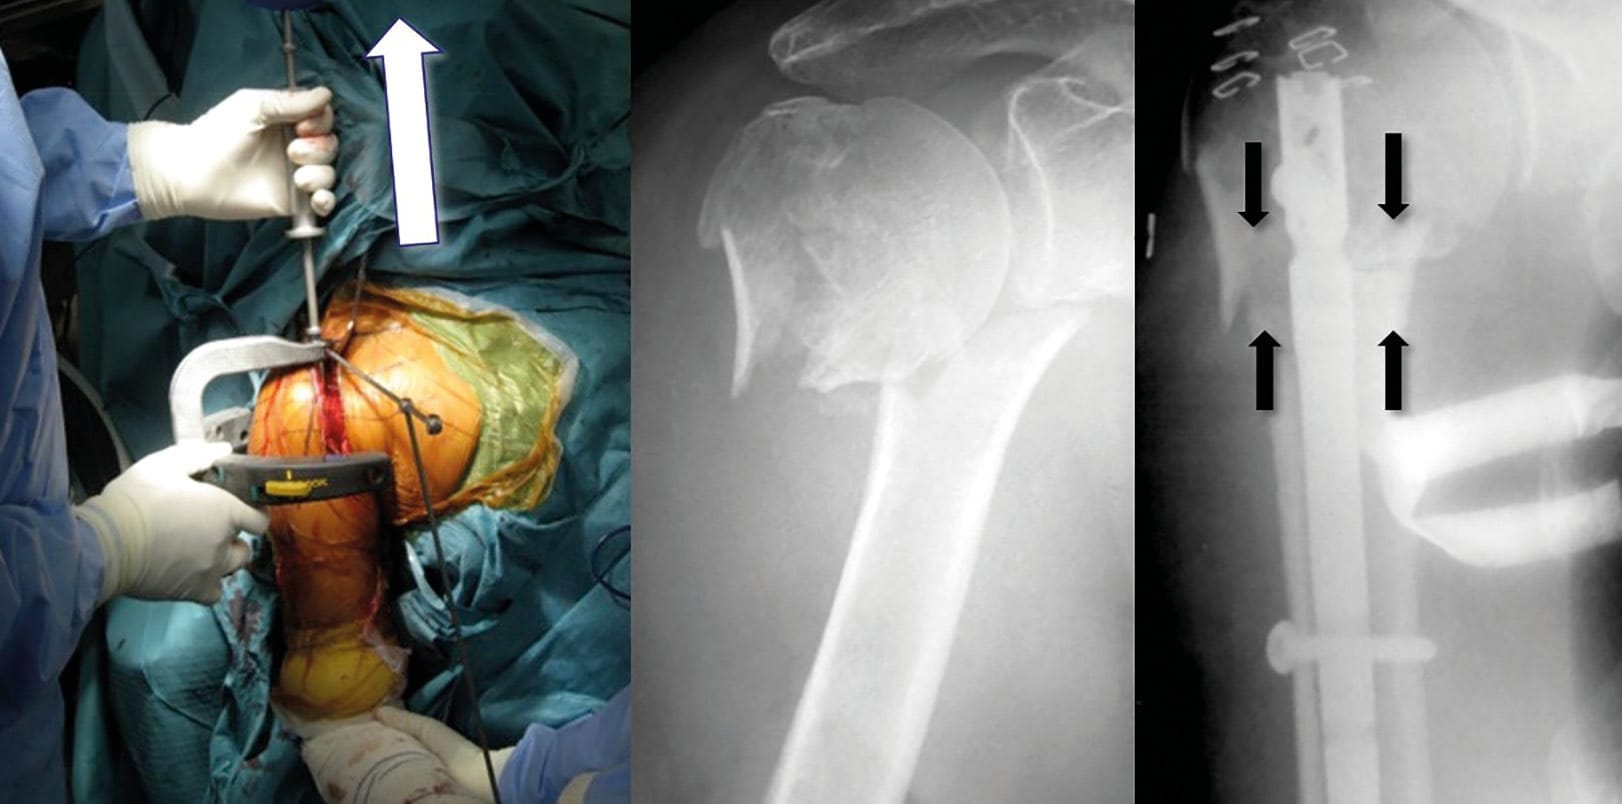

After assessment of the reduction and the nail’s depth under fluoroscopy, the guide wire is retrieved and the two distal screws were first placed in the diaphysis. Once distal fixation is obtained, gentle retrograde impaction of the distal to the proximal segment via a sliding slap-hammer is then performed (“backslap” hammering) to allow intraoperative immediate compression of the fracture site (Figure 5). Finally, proximal fixation is obtained by percutaneous insertion of a minimum of two proximal locking-screws via the attached jig. Postoperatively, the shoulder is placed in a sling for 1 week postoperatively. Passive elbow and shoulder mobilization with pendulum exercises (5 times a day and 5 minutes per session) is performed immediately. Patients are encouraged to remove the brace at day one, and to use their hand for ADLs.

At final follow-up, all fractures went onto union, and the mean humeral neck-shaft angle was 132° ± 5° (Figure 9). No cases underwent screw migration or intra-articular penetration. The mean correction of the angulation was 16.5°±8.3° (Table 1).

Our study shows that antegrade insertion of third-generation IMN through a percutaneous approach provides high rate of fracture healing, excellent clinical outcome scores with low rates of complications. Such IM nail has a low-profile and straight design, and the proximal screws are tuberosity-oriented and locked by polyethylene bushing inside the proximal part of the nail. We found several advantages for using this new generation of humeral IMN through a percutaneous approach for the treatment of displaced two-part surgical neck fractures, including minimal soft-tissue damage with minimal risk of humeral head osteonecrosis (only one case in our series), short operative time (42 minutes in average, including our learning curve) and improved cosmesis (Figure 9 and 10).